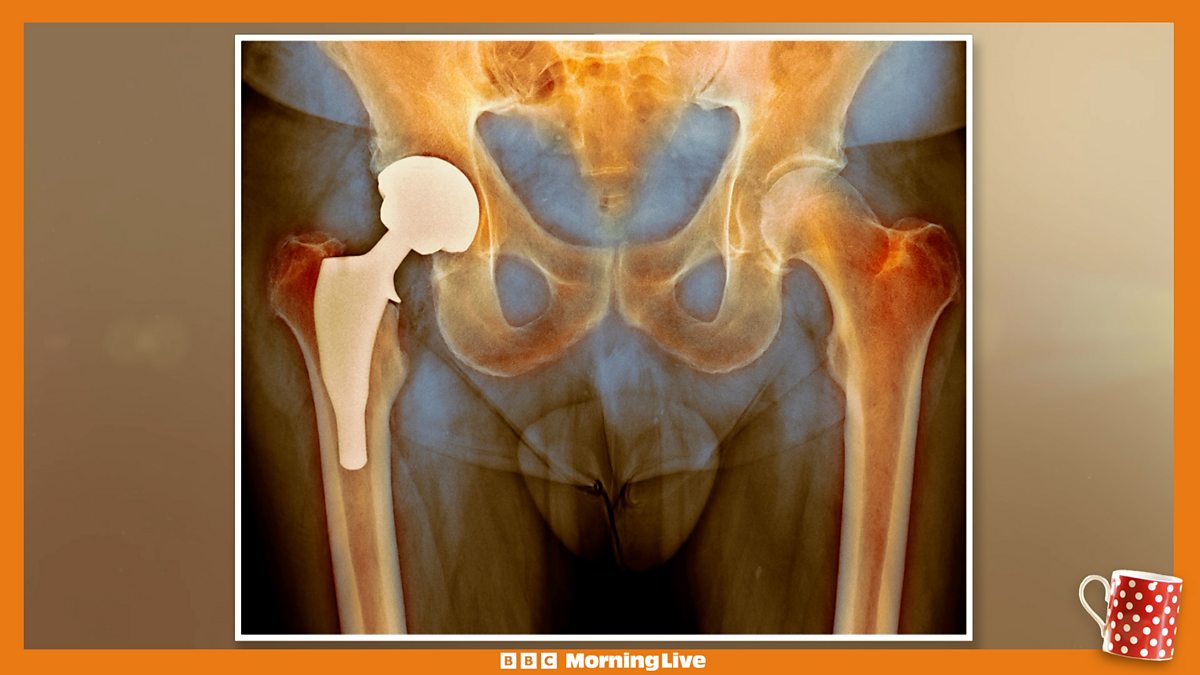

New figures show NHS waiting lists for hip and knee pain are driving a medical tourism boom. Overseas clinics are reporting an increase in Brits travelling to have procedures. Data from the Private Health Network shows the number of self-funded hip replacements has increased by over 160% since 2019. Dr. Xand talks about the dangers of medical tourism and Maria Tsiatsiani shows some simple exercises to keep your joints healthy.